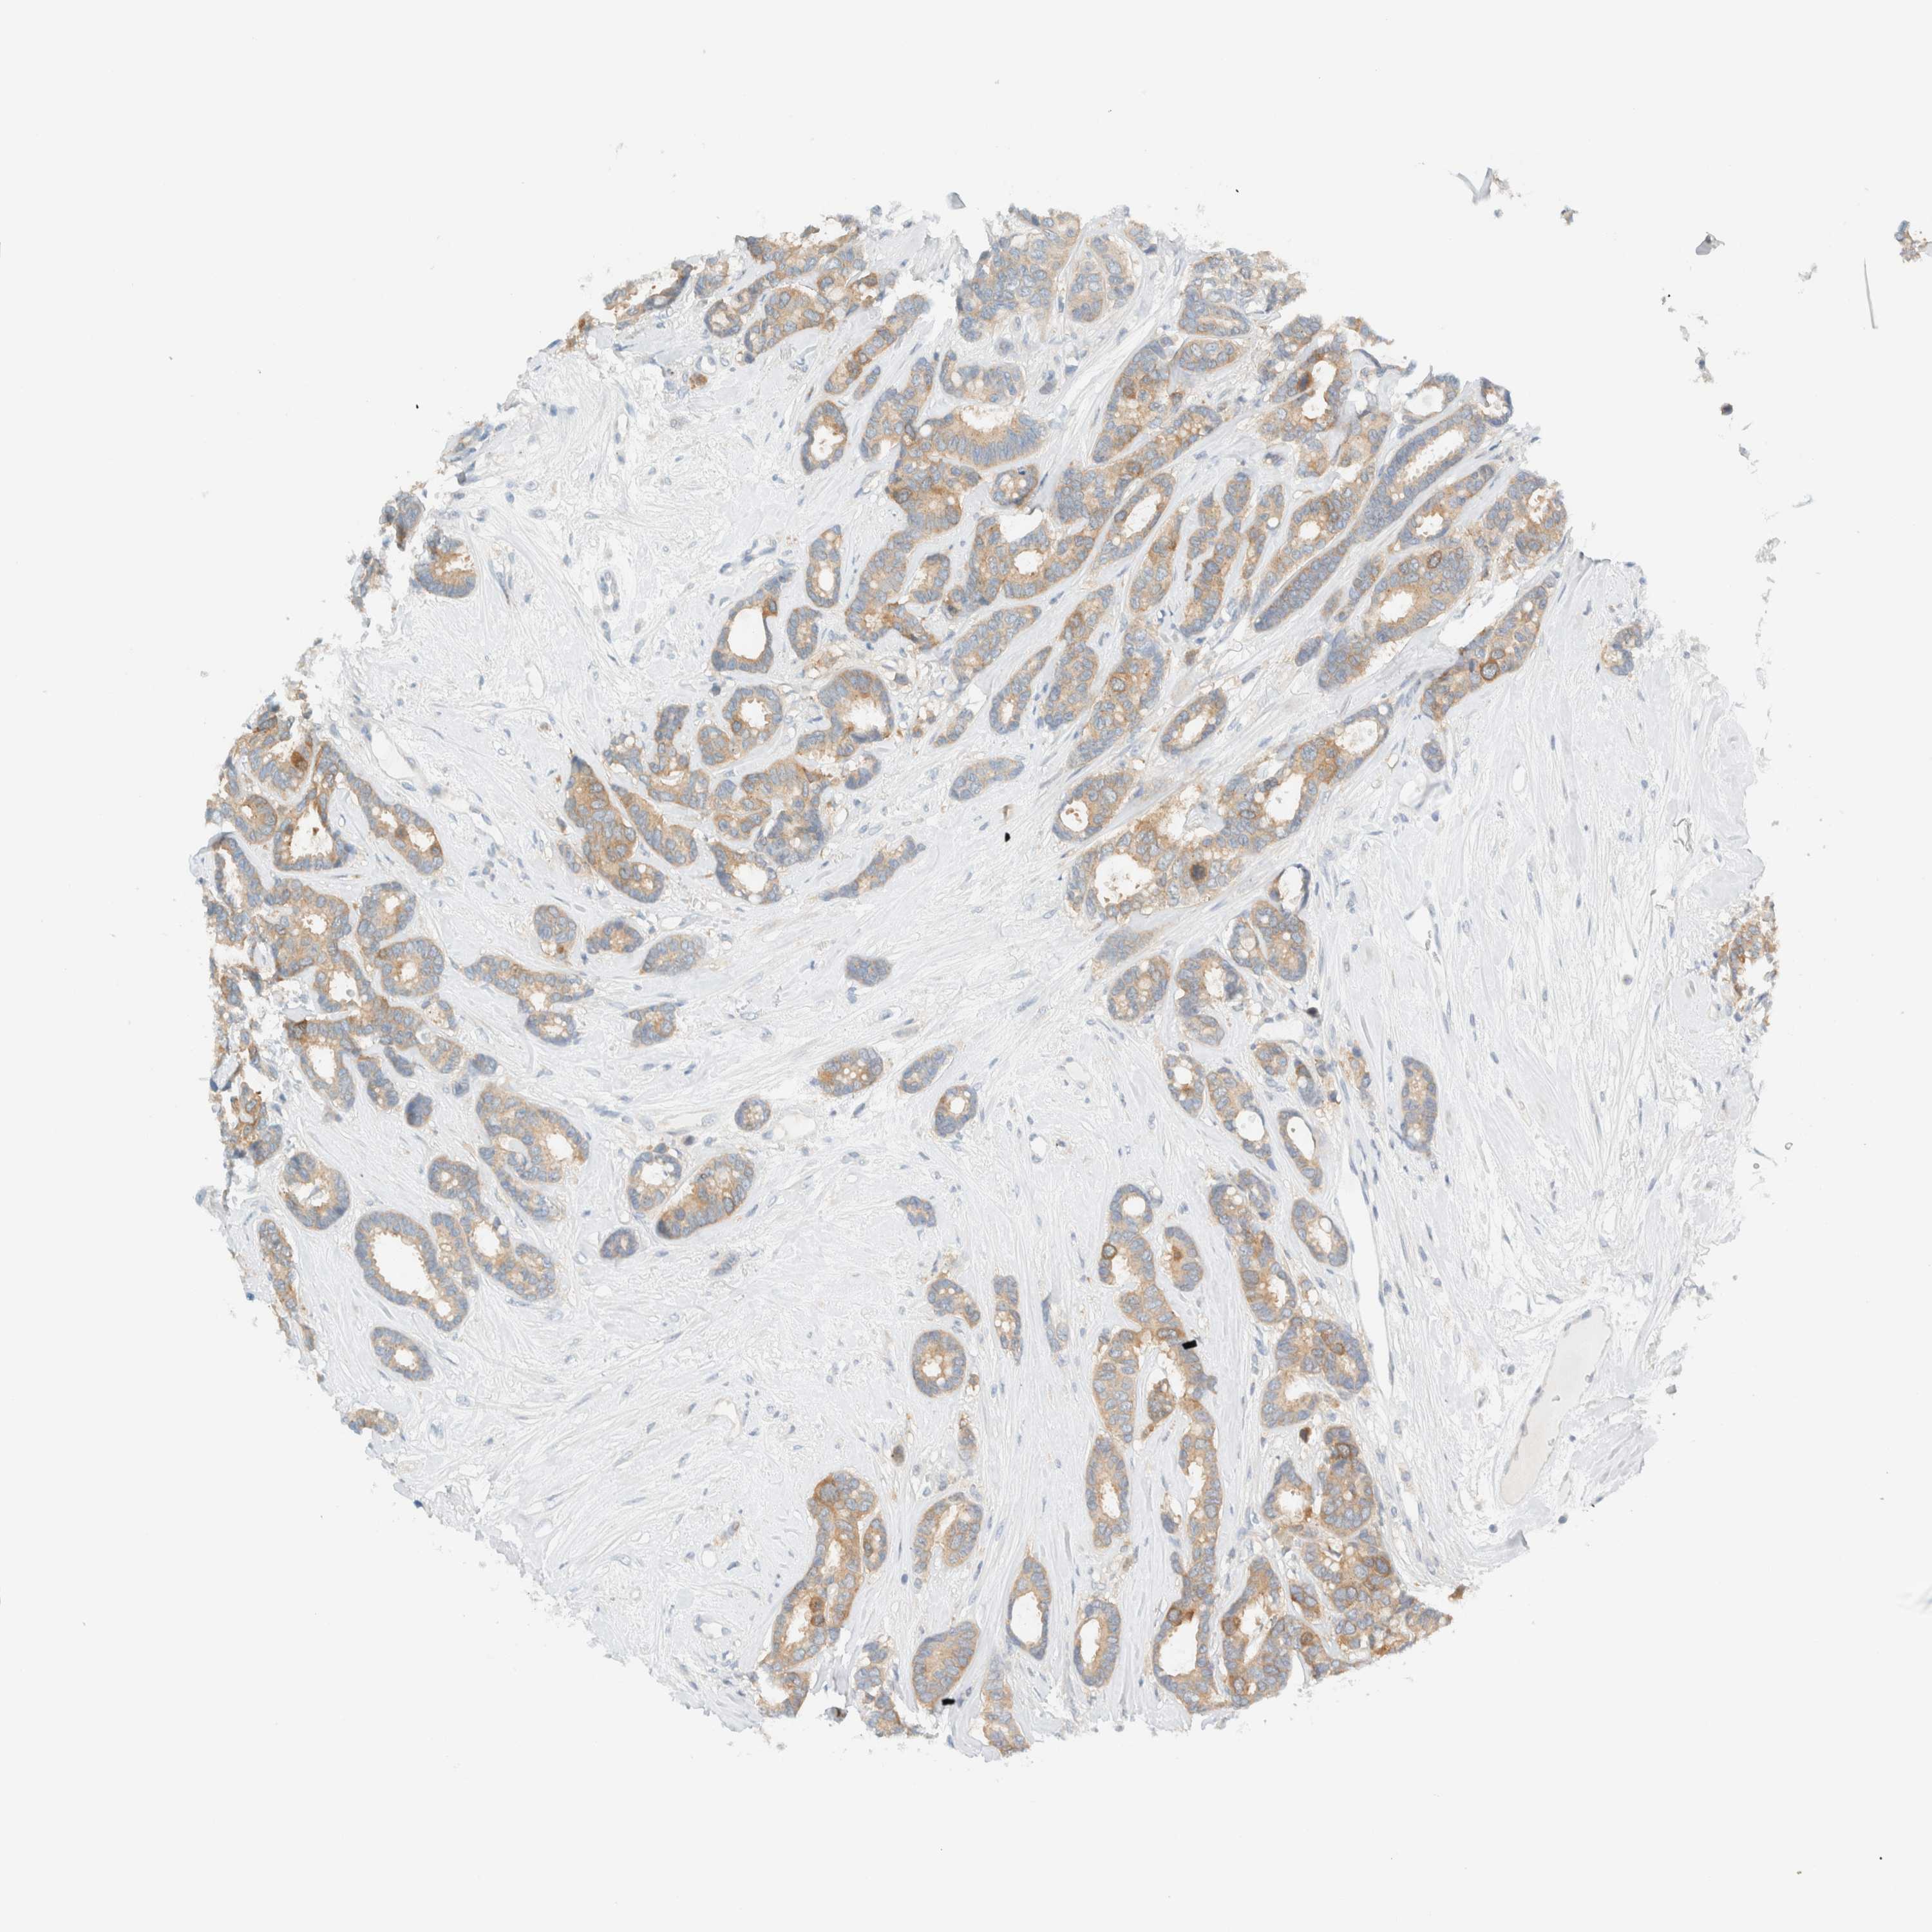

CANCER BREAST CANCER Show tissue menu

BRCA TCGA BRCA VALIDATION PROTEIN EXPRESSION